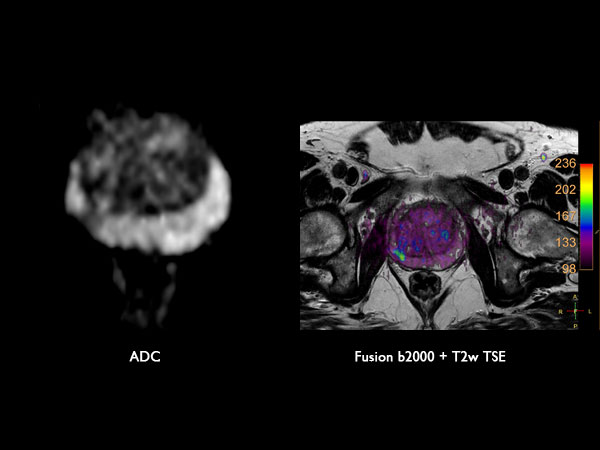

Axial Diffusion